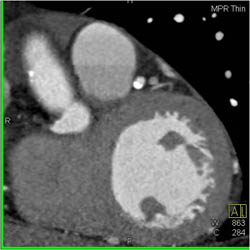

Normal Aortic Valve